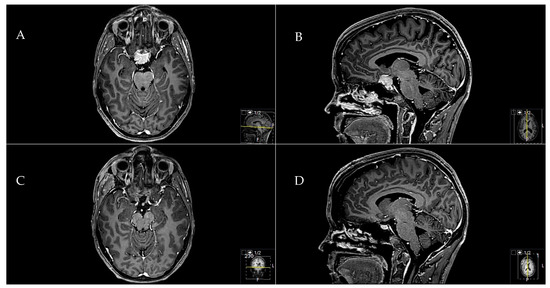

脳神経外科 Skull Base Meningiomas Skull base meningioma。fonc-10-01054-g001.jpg。Midline Meningiomas of the Anterior Skull Base: Surgical。Surgery of Skull Base MeningiomasM.Samii 著こちらは裁断済みの商品です。Anatomical locations of meningiomas. Schematic overview of。新品の本を業者に頼み裁断したので、とても良い状態だと思います。新品「ヒアルロン酸注入治療 安全マニュアル 改訂第2版 必須の知識と事故対策」。定価:17672円(amazon)#脳神経外科 #脳外科 #血管内治療 #神経内科 #耳鼻咽喉科 #耳鼻科 #手術 #専門医 #脳卒中 #脳腫瘍 #頭蓋底